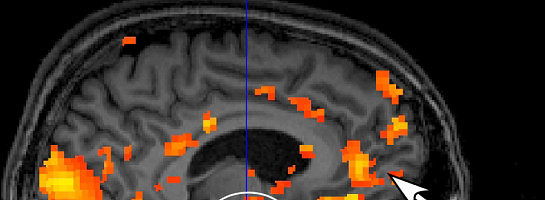

Evidence from ScienceResearcher Lucy Brown a professor of neurology at Albert Einstein College of Medicine, and her research partner of Rutgers University anthropologist, Helen Fisher, argues that the romantic love drive is even stronger than the sex drive.

In their study, they use an MRI machine to study the brains of the smitten. They observed that when people who are madly in Love think of their sweethearts, many parts of the brain are activated, but one thing all their study subjects had in common was activation in a "primitive" part of the brain just above the brainstem. This passion is part of one of our most profound, most important reward systems.